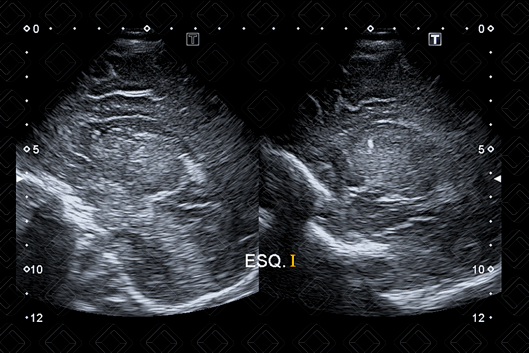

As imagens rotineiramente são obtidas nos planos coronal e sagital. As imagens coronais são obtidas colocando-se o transdutor transversamente pela fontanela anterior e angulando o feixe de ultrassom da frente para trás. As imagens sagitais são obtidas posicionando-se o transdutor em orientação longitudinal na fontanela anterior e angulando o feixe do meio para lateral (figuras 1 a 6).

Texto alternativo para a imagem Figura 1. Créditos: Dra. Elazir Mota - Rio de Janeiro/RJ

Texto alternativo para a imagem Figura 2. Créditos: Dra. Elazir Mota - Rio de Janeiro/RJ

Descrição das figuras 1 e 2: Ultrassonografia transfontanela cortes coronais, realizada varredura de anterior para posterior. CC – corpo caloso; Ch – plexo coroide; [cms-watermark] F – lobo frontal; N – núcleos da base; [cms-watermark] T – lobo temporal.